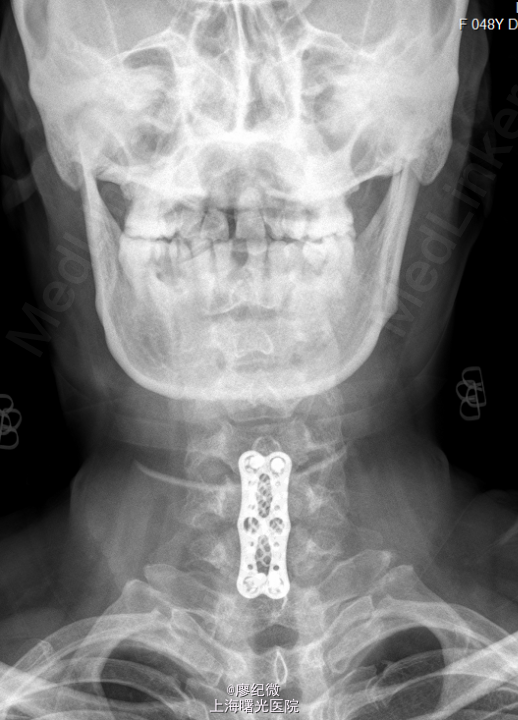

初步诊断:颈椎病. 处理: 全麻麻醉下行“[颈椎]颈椎前路减压融合内固定术”. 作右颈前上斜切口长约6cm,逐层切开皮肤、皮下组织、颈阔肌,自胸锁乳突肌内侧钝性分离,分离直达颈椎前方。经C形臂影像增强器透视确定C6椎体,剥离椎前筋膜和前纵韧带,显露椎体前方,于C7、C5椎体上各置入撑开螺钉1枚,撑开器适当撑开,彻底清除C5/6、C6/7椎间盘,减压彻底后,予以冲洗。取合适大小钛网植入,前方放置一块钢板,C7、C5椎体各攻入两枚螺钉,并予以自锁。经C形臂影像增强器透视位置理想,螺钉长度合适。